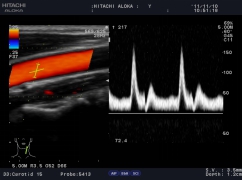

通過復(fù)合陣列探頭及SIP、AIP等多種成像技術(shù),為臨床帶來優(yōu)質(zhì)的二維圖像和敏感的血流,可以更加真實(shí)的反映血管的灌注情況,真實(shí)再現(xiàn)微細(xì)血管解剖形態(tài)。

作為原裝進(jìn)口的全身應(yīng)用型高檔全數(shù)字化彩色多普勒超聲診斷系統(tǒng),它在腹部、泌尿、婦產(chǎn)、乳腺、甲狀腺、淺表、腔內(nèi)、心臟等各個領(lǐng)域都有完美的圖像表現(xiàn)及豐富的應(yīng)用支持。